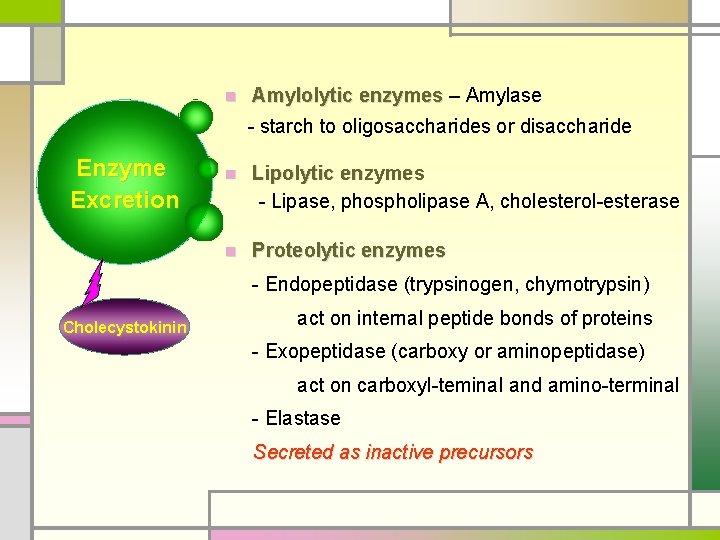

n Amylolytic enzymes – Amylase - starch to oligosaccharides or disaccharide Enzyme Excretion n Lipolytic enzymes - Lipase, phospholipase A, cholesterol-esterase n Proteolytic enzymes - Endopeptidase (trypsinogen, chymotrypsin) Cholecystokinin act on internal peptide bonds of proteins - Exopeptidase (carboxy or aminopeptidase) act on carboxyl-teminal and amino-terminal - Elastase Secreted as inactive precursors